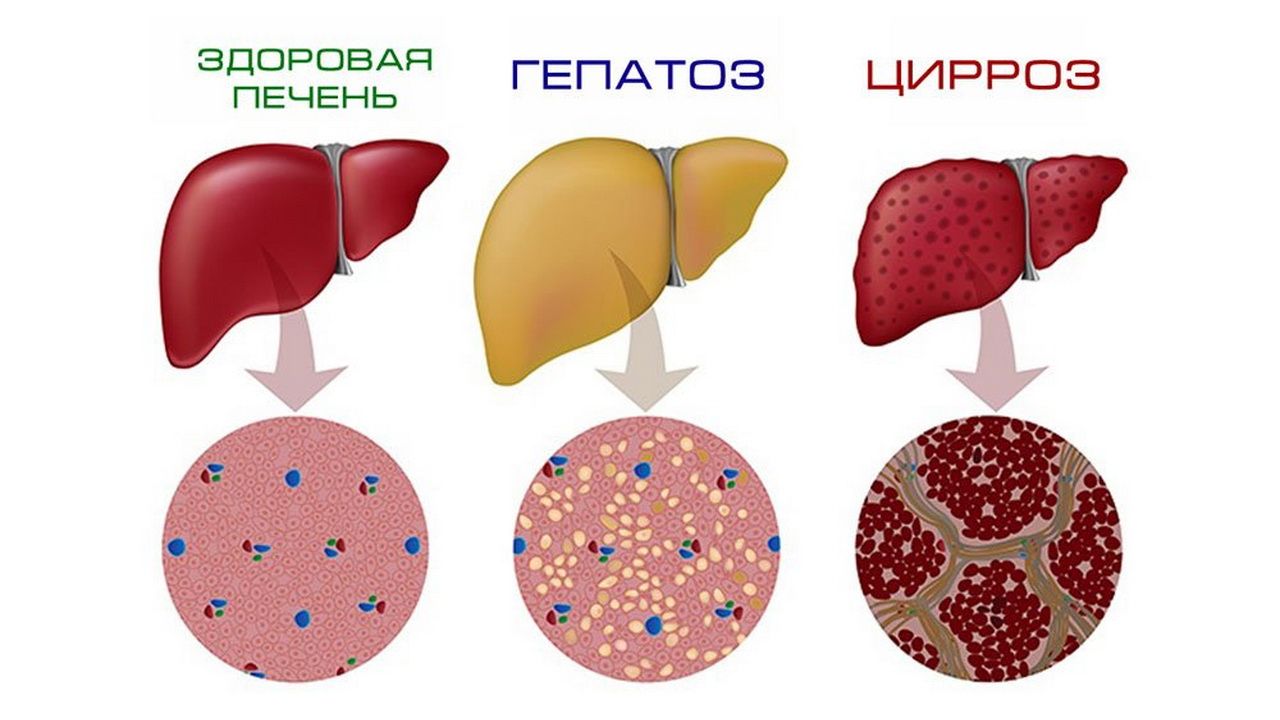

Практические советы по лечению ожирения печени в домашних условиях

Жировой ГЕПАТОЗ : причины, симптомы, ДИЕТА и ЛЕЧЕНИЕ. Ожирение печени: что делать.